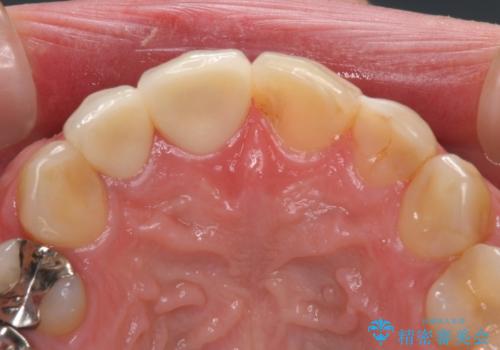

上の前歯など審美性の要求が高くなる部位については、数本同時に製作することで色をそろえることが可能です。

患者様は前歯の見た目の改善を主訴にご来院されました。上の前歯6本とも古いつめものがつぎはぎになっていましたが、まずは1番目立つところを治すことをご希望でした。相談の結果、今回は2本できれいになるように工夫しました。

患者様には大変満足して頂きました。